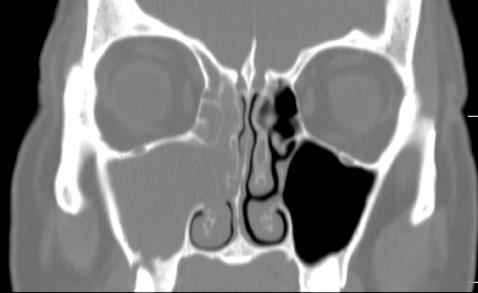

| A coronal CT 2 months after ethmoid and maxillary sinus surgery showing complete resolution of sinus disease. |

|

| Several months later, she underwent a successful sinus lift with implantation and a coronal CT image demonstrating ossification of the sinus augmentation. |